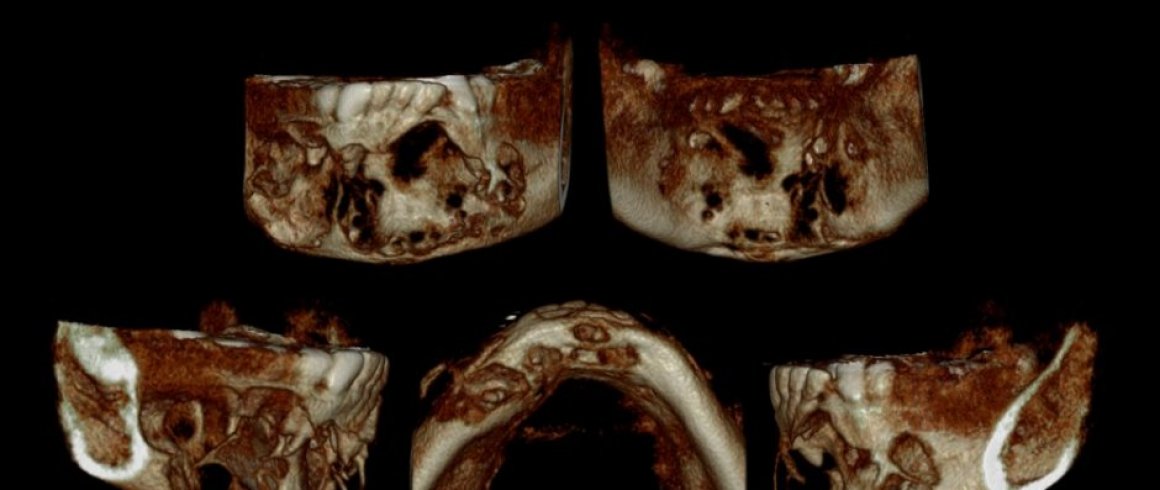

- Tomografía

- Implantes

- A.T.M. (Boca abierta/Boca cerrada)

- Localización de Diente Impactado

- Área Patológica